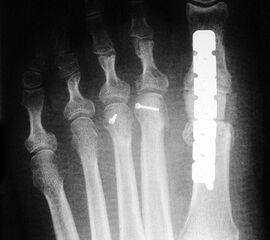

Die Röntgenaufnahmen (Abbildung 1) zeigen den Fuß einer 34 jährigen Patientin nach Exostosenabtragung. Der erhöhte intermetatarsale Winkel wurde durch eine alleinige Abtragung der Exostose nicht reduziert. Als weiterer Risikofaktor für ein Rezidiv liegt ein pathologischer Gelenkwinkel vor. Der intermetatarsale Winkel von 18 Grad kann durch eine basisnahe Osteotomie gut korrigiert werden. Da durch die gleichzeitige distale Korrektur des Gelenkflächenwinkels mithilfe einer Reverden-Green Osteotomie ein Längenverlust von ca. 2-4 mm einhergeht, bot sich als proximales Korrekturverfahren die basisnahe Open-wedge Osteotomie an, um bezüglich der Länge des Metatarsale I neutral zu bleiben (Abbildung 2). Die Kombination zweier verkürzender Verfahren (z.B. Lapidus und Reverden-Green) würden zu einem sehr kurzen ersten Strahl führen, mit dem Risiko einer Transfermetatarsalgie. Übersteigt die Verkürzung des Metatarsale I 2 mm, steigt das Risiko für die Entwicklung einer Transfermetatarsalgie deutlich an 8. Die durchgeführte Revision zeigt eine gute Stellung des 1. Strahls bei zentriert stehendem Gelenk.